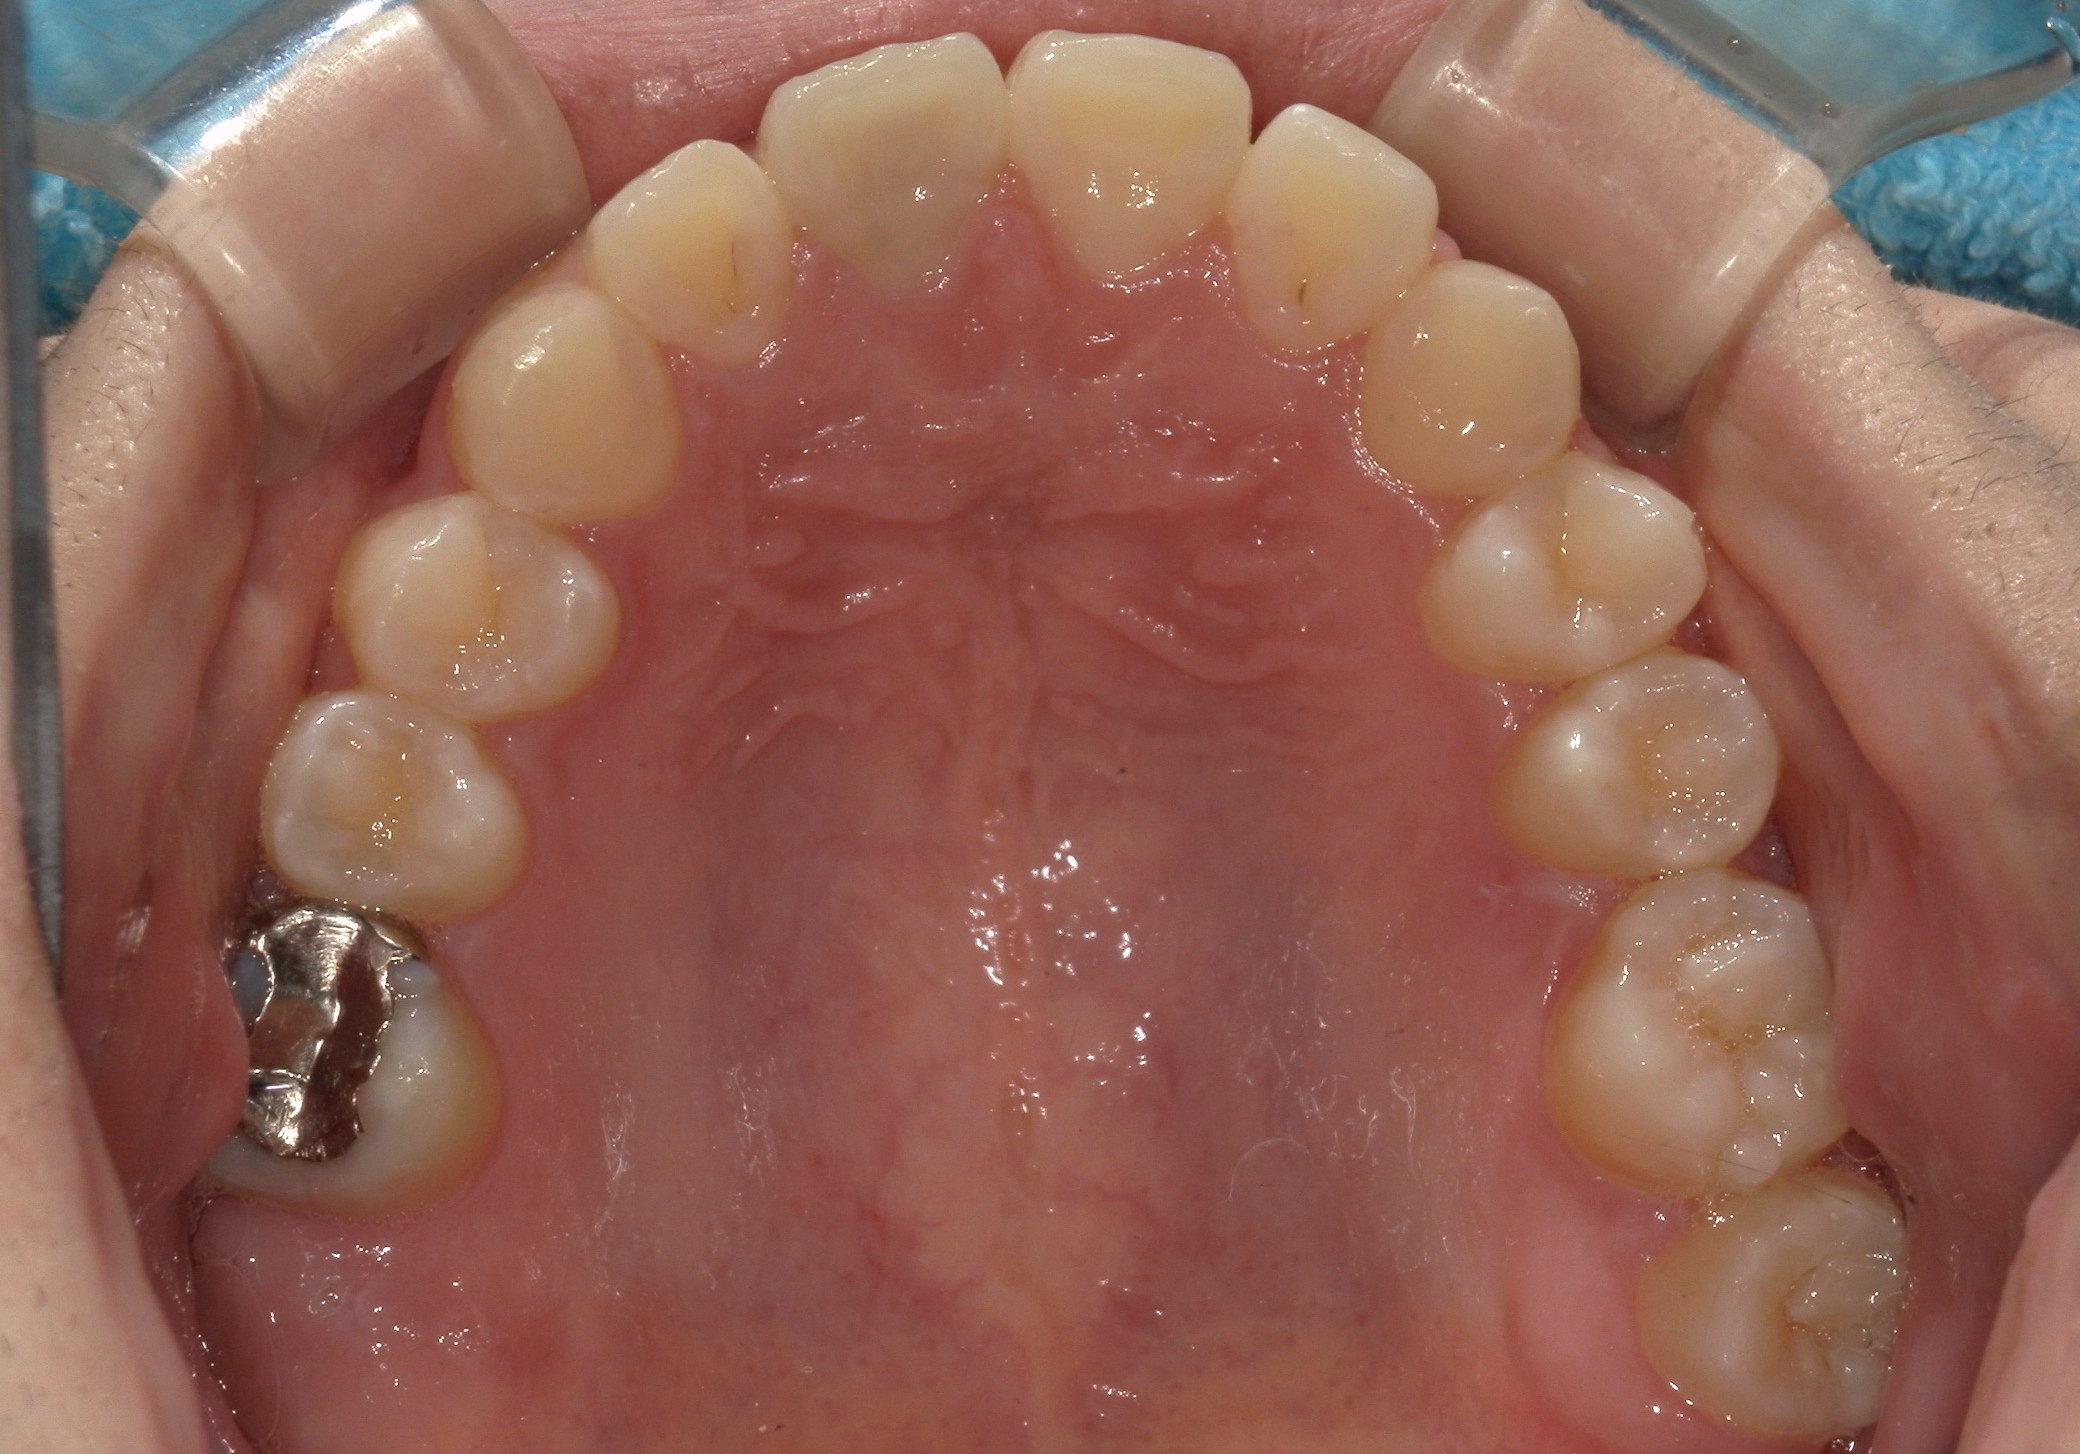

矯正術後:上顎